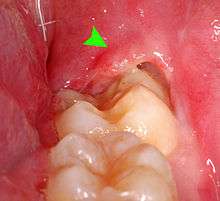

Pericoronitis is inflammation of the soft tissues surrounding the crown of a partially erupted tooth.[24] The lower wisdom tooth is the last tooth to erupt into the mouth, and is, therefore, more frequently impacted, or stuck, against the other teeth. This leaves the tooth partially erupted into the mouth, and there frequently is a flap of gum (an operculum), overlying the tooth. Bacteria and food debris accumulate beneath the operculum, which is an area that is difficult to keep clean because it is hidden and far back in the mouth. The opposing upper wisdom tooth also tends to have sharp cusps and over-erupt because it has no opposing tooth to bite into, and instead traumatizes the operculum further. Periodontitis and dental caries may develop on either the third or second molars, and chronic inflammation develops in the soft tissues. Chronic pericoronitis may not cause any pain, but an acute pericoronitis episode is often associated with pericoronal abscess formation. Typical signs and symptoms of a pericoronal abscess include severe, throbbing pain, which may radiate to adjacent areas in the head and neck,[20][25]:122 redness, swelling and tenderness of the gum over the tooth.[26]:220–222 There may be trismus (difficulty opening the mouth),[26]:220–222 facial swelling, and rubor (flushing) of the cheek that overlies the angle of the jaw.[20][25]:122 Persons typically develop pericoronitis in their late teens and early 20s,[27]:6 as this is the age that the wisdom teeth are erupting. Treatment for acute conditions includes cleaning the area under the operculum with an antiseptic solution, painkillers, and antibiotics if indicated. After the acute episode has been controlled, the definitive treatment is usually by tooth extraction or, less commonly, the soft tissue is removed (operculectomy). If the tooth is kept, good oral hygiene is required to keep the area free of debris to prevent recurrence of the infection.[20]:440–441